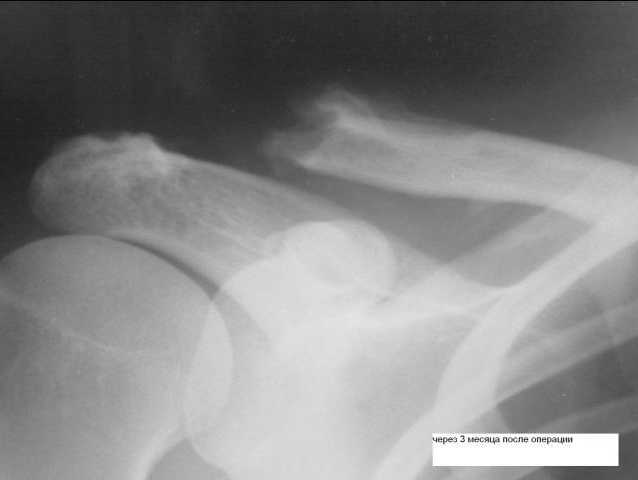

из

прошу консультаций по дальнейшей тактике лечения, кто что предложит, пациентка анастаивает на повторной операции - устранении вывиха ключицы. клинически - умеренная деформация - выстояние ключицы. признаков воспаления нет.